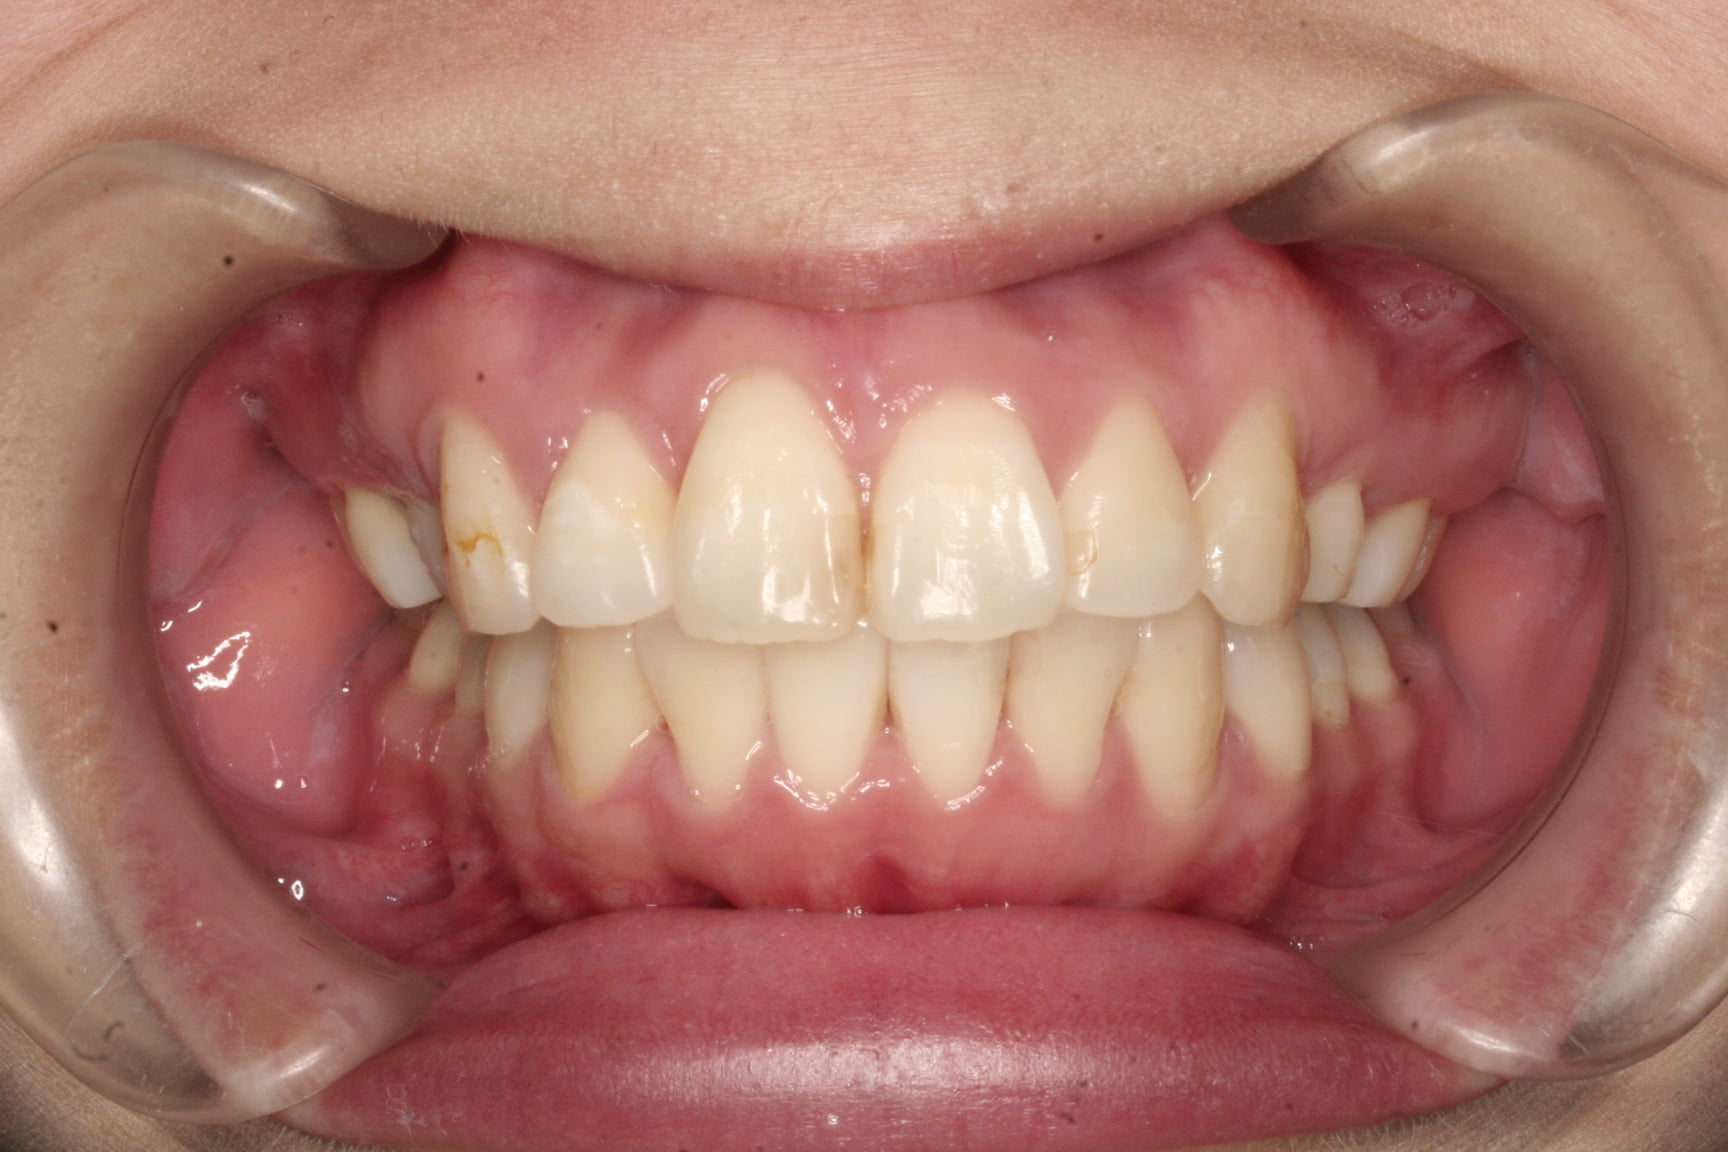

出っ歯を治したい

年齢層 30代

性別 女性

主訴 【主訴】出っ歯を治したい 【診断・症状】上下凸凹、口元が出てる

治療費用 検査・診断:38,500-/裏側矯正治療:1,397,000-(※全て税込)

治療期間 約2年9か月(36回)

抜歯 抜歯:有(上4,4)

矯正の装置 裏側矯正(舌側矯正)

副作用、リスク 歯肉退縮,歯根吸収,疼痛,咬合の違和感,装置の違和感,虫歯,歯肉炎

case21_出っ歯_before

Before

case21_出っ歯_after

After